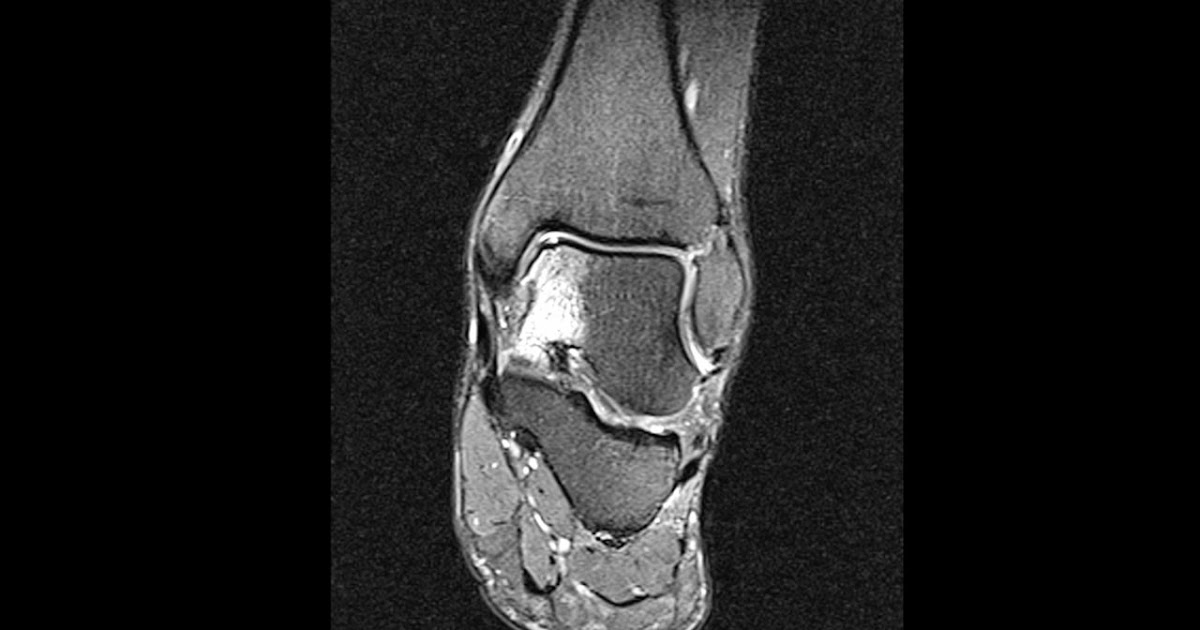

a. MR imaging indicated bone marrow edema of the proximal tibia, distal

Casos de radiología de la Clínica Universidad de Navarra: Caso 228

Source: radiodiagnosticocun.blogspot.com